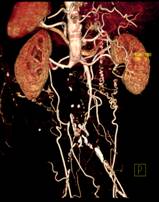

320排螺旋CT具备16cm宽覆盖探测器,实现动态容积扫描,360度的各向同性采集能力及[email protected]%密度分辨率的量子探测器,一次心跳全心脏采集,一圈扫描器官成像,一次检查完成多重任务,实现真正的动态容积体灌注及心脏、神经一站式检查;西门子Flash炫速CT扫描系统,具备两套同时旋转的X射线球管及探测器,实现了43cm/s的极快CT扫描速度和75 ms的时间分辨率,完成全胸扫描仅需0.6秒,使得患者做心脏扫描时无须食用β-受体阻滞药,亦无须屏气,并可实现低于1mSv的超低辐射剂量,配置第二代双能量、宽151级纯化能谱,组织鉴别能力进一步提高,可开展多达10余种双能量成像应用。

肝脏、胰腺、肾脏CT-DSA 及灌注功能一站式检查

先天性血管性疾病的血流动力检查